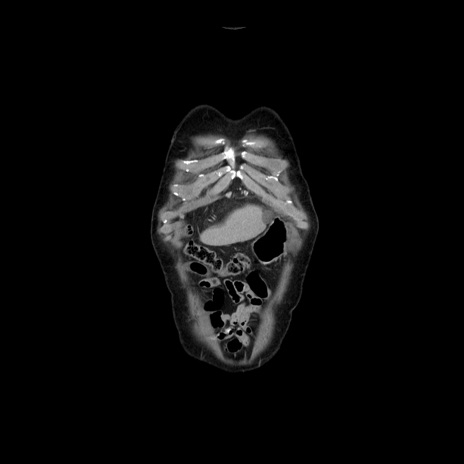

横断像

【症例】70歳代男性

【主訴】腹痛

【現病歴】肝硬変・肝細胞癌にてかかりつけの方。約9時間前に食後より腹痛出現。症状が徐々に増悪し、嘔吐出現したため来院。

【既往歴】肝硬変、肝細胞癌(RFA、TACE後)

【身体所見】意識清明、表情苦悶様、BT 36℃、BP 129/78mmHg、P 88bpm、SpO2 97%(RA)、右上腹部から心窩部にかけて圧痛あり、反跳痛なし、筋性防御あり。

【データ】WBC 5800、CRP 0.16